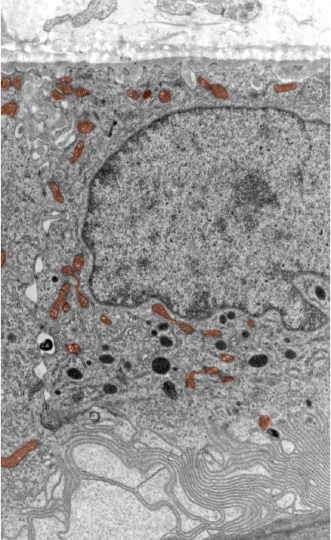

Mitochondria, shown here in brown in this electron micrograph, provide the energy a cell needs to function.

Every tissue has unique metabolic demands. Some parts of the body require more energy and nutrients to operate than do other parts of the body. The retina is a highly metabolic tissue, and one that experiences unique stresses due to its function as a light-sensing tissue. Defects in metabolism contribute to age-related neurodegenerative diseases, and could play a role in MacTel. The Lowy Medical Research Institute has a research program dedicated to the study of metabolism in the retina in general, and in MacTel patients specifically.